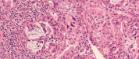

UofG scientists to lead multimillion pound research project into bowel cancer treatments